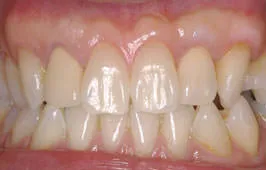

Before

根面被覆術治療例

After

根面被覆を行うことにより知覚過敏の症状が回復しました。